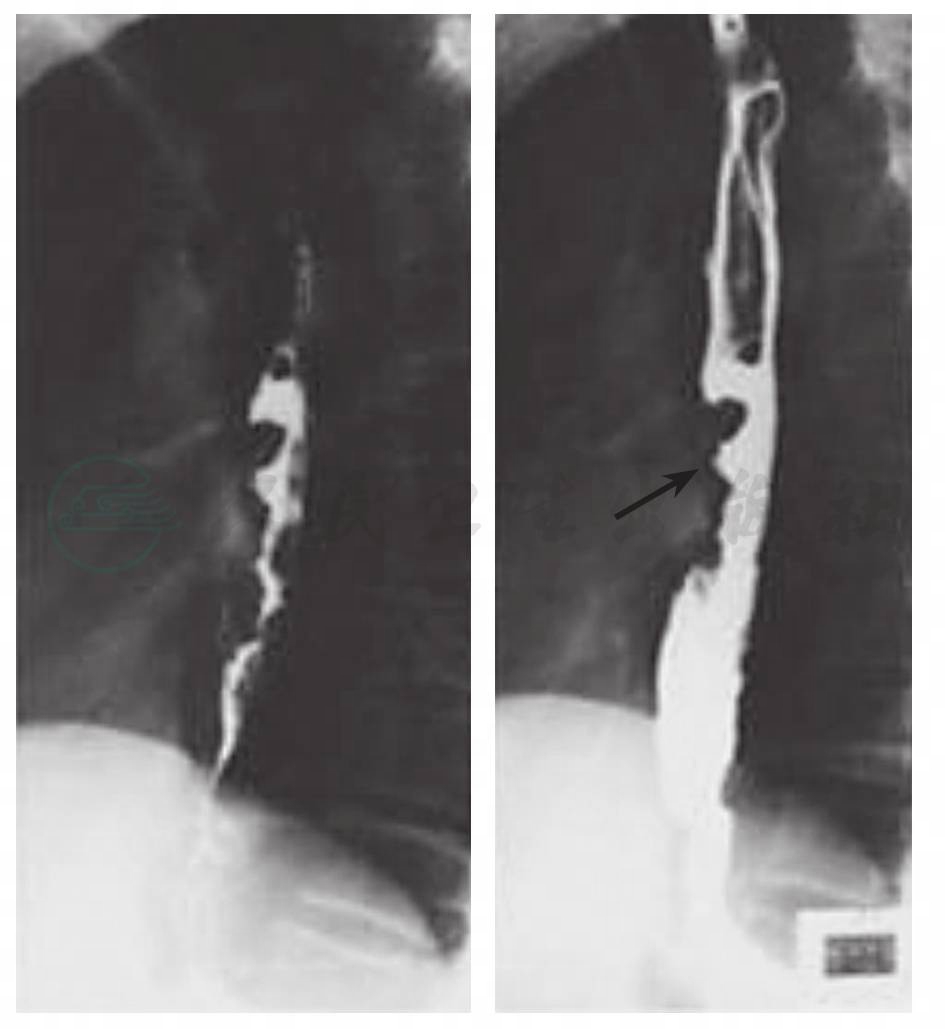

食管钡餐造影(图2):患者吞食硫酸钡后,对钡剂流经食管的过程进行X线照射,可显示食管狭窄的部位及程度。

图2钡餐造影显示食管狭窄段